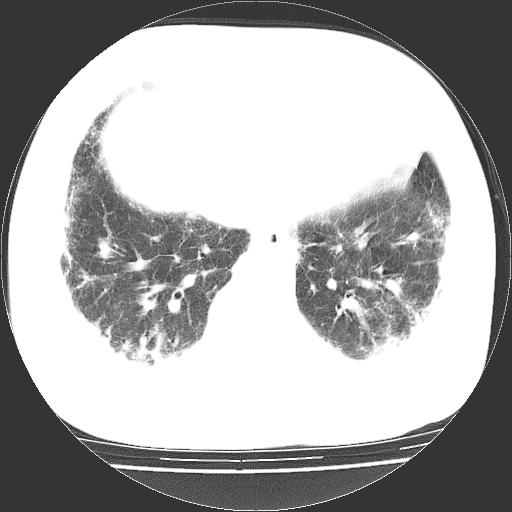

男,68岁,咳嗽、胸闷、发烧三天,查体:双肺散在湿罗音。

首先考虑特发型肺间质纤维化;两侧少量胸腔积液。

依据:1、两肺广泛条索状、网格状、蜂窝状改变。

鉴别诊断:肺结核:病灶呈多形性改变,往往纤维化较多的病例,经常会有空洞;本例不大符合。

慢性支气管炎伴感染:临床病史不大支持,而且往往肺气肿较明显,本例不大明显。

根据3天的病史考虑 肺部感染,间质肺炎可能性大,网格及蜂窝影提示病灶时间较长结合肺纹混乱支持慢支炎,肺间质纤维化,肺心病,双侧胸腔积液。抗炎治疗复查

现在胸部出现了很多类似片子 首先侵犯肺间质 其次影响肺组织 肺组织成毛玻璃样 甚至实变但肺纹理在其中清晰可见 有的连点胸腔积液也没有 临床以发烧气喘胸闷为主 病人大都以呼吸衰竭走向马克思 临床治疗上也没什么好方法 ct诊断也感觉棘手 大都以间质肺炎结论 我感觉向这样的病人他死了可能最后也不知道怎么死的 只希望有条件的医院可以通过肺组织活检追查原因 从我看过的片子中有很多病人临床是免疫低下现象 有很多爱滋病患者最后的肺部表现出现类似图象 有机会我传上几张 大家共讨

双肺多发条索状、网格状及小灶状密度增高影。考虑慢支合并感染.间质纤维化,双侧少量胸腔积液

两肺广泛条索状、网格状、蜂窝状改变。肺间质纤维化,肺心病,双侧胸腔积液